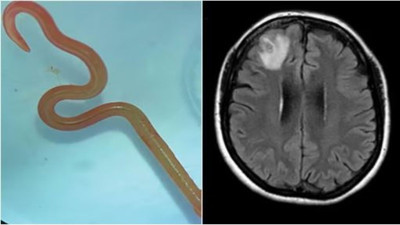

Hastanın beyninden solucan çıktı. Tıp dünyası şokta Avustralya’da bir kadının beyninden çıkan solucan tüm tıp dünyasını şoka uğrattı. Daha önce böyle bir vakanın görülmediği bildirildi.

Unutkanlık ve depresyon şikayetiyle hastaneye gitti. Beyninden solucan çıktı Unutkanlık ve depresyon şikayeti ile doktora giden 64 yaşındaki kadının beyninden sekiz santimlik canlı bir solucan çıkarıldı.